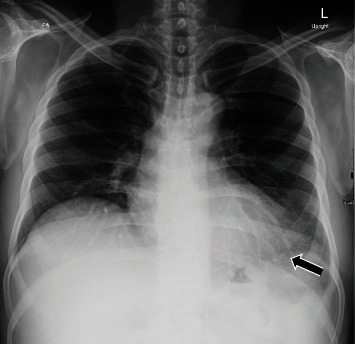

背景:新冠肺炎疫苗临床试验报告了mRNA疫苗(阿斯利康)帮助控制疾病的安全性和有效性。以前很少有报告显示与COVID-19疫苗相关的各种副作用,其严重程度各不相同。在接受我们报告的mRNA COVID-19疫苗的人群中观察到心包炎和心肌炎的可能性。急性炎症性心包炎在首次接种该疫苗后可能是一种罕见的症状,在COVID-19时代分享这种罕见的症状对于更好地管理和接种疫苗后的结果是有益的。案例演示。这是一例健康成人患者在接受阿斯利康COVID-19疫苗第一剂后出现急性炎症性心包炎伴少量心包积液的病例,除COVID-19 PCR阴性外,无其他提示其他病毒性疾病的症状。一名48岁的健康男性在接种第一剂新冠肺炎阿斯利康疫苗9天后出现。该症状始于接种疫苗后3天,当时他主诉进行性胸痛,伴有低烧和全身乏力,几天后出现用力性呼吸困难。诊断为急性炎症性心包炎伴少量心包积液,并给予相应治疗。一星期后,病人的临床表现明显改善,心包积液得以消除。39天后,急性心包炎的影像学表现明显好转。结论:目前正在进行的COVID-19疫情仍在调查中,尽管多种疫苗已被证明对COVID-19有效,但由于我们不断了解这种新型疾病,指南仍在定期修改。然而,我们报告了一例在首次接种阿斯利康COVID-19疫苗后出现独特临床表现的病例,在文献中尚未广泛报道,这可能有助于提高人们对COVID-19疫苗接种后可能诊断和炎症性心包炎可能性的认识。

Background: Clinical trials of the COVID-19 vaccine reported the safety and efficacy of mRNA vaccines (AstraZeneca) to help control the disease. Few previous reports have shown various side effects associated with COVID-19 vaccines that vary in severity. The possibility of pericarditis and myocarditis has been observed in people who have received an mRNA COVID-19 vaccine which we are reporting. Acute inflammatory pericarditis can be a rare presentation after receiving the first dose of this vaccine, and it is enriching to share such rare presentations in the era of COVID-19 for better management and outcomes after vaccination. Case Presentation. This is a case of acute inflammatory pericarditis with a small pericardial effusion after receiving the first dose of AstraZeneca COVID-19 vaccine in a healthy adult patient who had no other symptoms suggestive of other viral illness in addition to the negative COVID-19 PCR. A 48-year-old healthy male presented nine days after receiving the first dose of COVID-19 AstraZeneca vaccine. The symptoms started three days after the vaccine, when he complained of progressive retrosternal chest pain with low-grade fever and generalized fatigue, followed by exertional dyspnea after a few days. The diagnosis of acute inflammatory pericarditis with small pericardial effusion was established, and the patient was accordingly treated. One week later, the patient showed significant clinical improvement with the resolution of his pericardial effusion. After 39 days, there was a significant radiological resolution of signs of acute pericarditis.